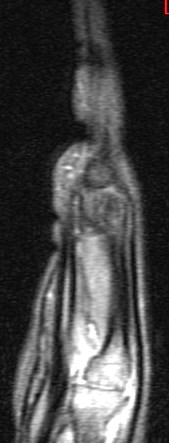

14 y/o with history of bilateral wrist pain.

His carries a known diagnosis of Juvenile Rheumatoid Arthritis. (RID3610) New term is JIA. He has failed steroid therapy and methotrexate. Currently on humira. R/O osseous change. Its ruled in. Reference article.

Juvenile idiopathic arthritis